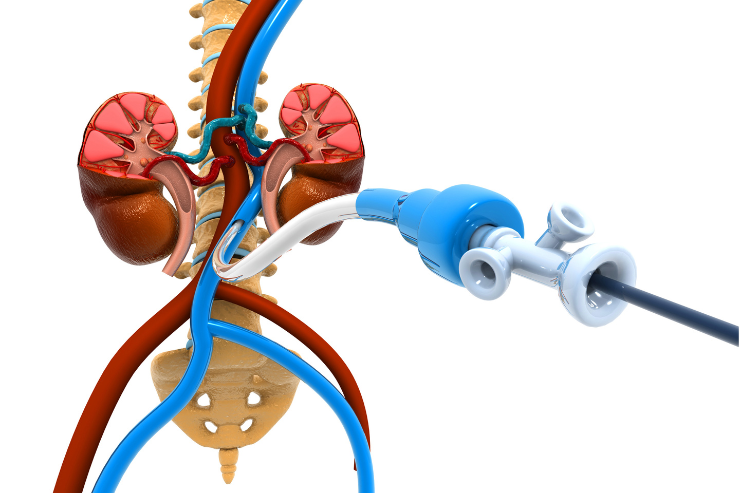

Prostate Artery Embolization

Prostate Artery Embolization is a minimally invasive procedure used to treat benign prostatic hyperplasia (BPH). It involves injecting small particles into the arteries supplying the prostate to block blood flow, causing the prostate to shrink. This reduces symptoms such as frequent urination and urinary obstruction, improving quality of life for patients with BPH.